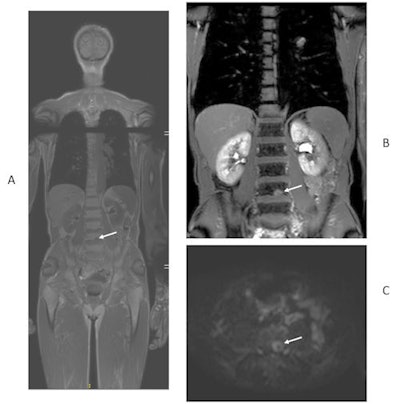

Fresh evidence shows that whole-body MRI may be quicker and cheaper than standard imaging for detecting the spread of colorectal and non-small cell lung cancers, while being just as sensitive. The findings from two prospective trials involving nearly 500 patients across 16 U.K. hospitals were published on 9 May in Lancet Gastroenterology & Hepatology and Lancet Respiratory Medicine.

In patients with newly diagnosed colorectal and non-small cell lung cancer, Taylor and colleagues found that whole-body MRI scans reduced the average time to determine the size of tumors and how much they had spread by five days for colorectal cancer patients and six days for lung cancer patients. The treatments decided upon were similar because results from MRI were as accurate as those from standard investigations, but the costs per patient were reduced by nearly a quarter in the case of colorectal cancer and were almost halved for lung cancer.